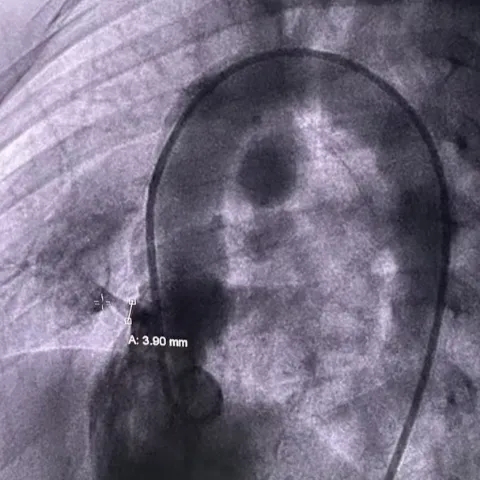

术中造影

术中造影复测缺损左室面破口3.9mm,隧道长11.37mm,判定为长隧道型室间隔缺损。